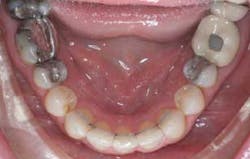

There are numerous studies that correlate an increase in Little’s Irregularity Index (incisor crowding) and an increase in the gingival index and plaque index. (1) Crowded teeth, as expected, are much harder to maintain than aligned incisors. (2) Increased plaque index and gingival index are seen on the lingual of mandibular incisors that are misaligned. All patients have an increase of calculus buildup on the lingual of their incisors. However, when the lower incisors are crowded and crooked, they are not easily flossed or brushed. (3) This also can allow for food impaction, occlusal prematurities, and difficult access.

By correcting these issues, a patient (and our team) has the ability to restore these teeth to healthy function.